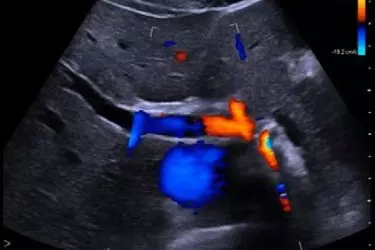

Color Doppler ultrasound is an imaging technique which is used to provide visualization of the blood flow in the arteries and the veins. With the advent of Medical Technology, CT and MRI angiography has emerged as the preferred diagnostic modality for study of blood vessels. In angiography iodine based contrast agent is used which is harmful for kidneys. In comparison a colour doppler study is perfectly safe even for pregnant women as there is no radiation involved and safe for patients of kidney disease as there is no iodine involved.

Colour Doppler is of great use in pregnancy for seeing the position of the umbilical cord, for studying the valves and coronary arteries through 2-D Echocardiography, Renal artery by doing Renal Colour Doppler, Arteries and Veins of the hands and legs to see any blockages in them. Carotid artery for seeing the blockages in the blood going to the brain. The colour doppler study is not only harmless to the body but also a cost effective way of diagnosing the diseases of the blood vessels.

Vascular Color Doppler - Several Medical conditions causes the arteries and veins to become narrow. This reduces the blood supply to different body parts. Arterial and Venous Colour Doppler studies are done mostly for the upper and lower limbs to determine the blockages in the vessels and determine the extent of narrowing of these vessels